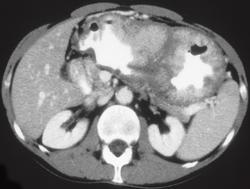

Carcinoma of the Gastric Antrum